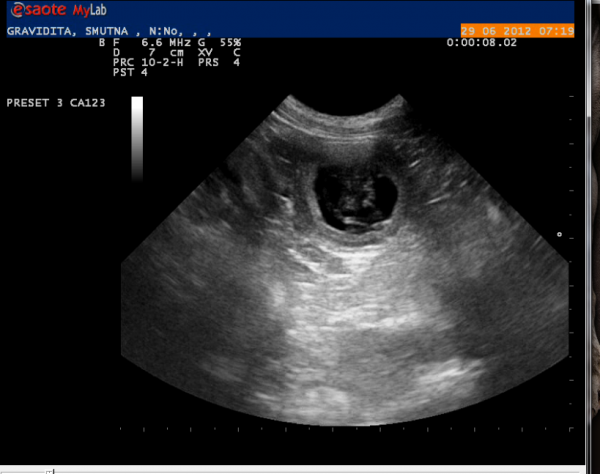

březost potvrzena, z Emuláka bude mamina!!

V pátek nám sonograf potvrdil březost - čekáme minimálně šest malých šedivých kuliček!!!! všem tlučou srdíčka, vše je v naprostém pořádku. Držte nám pěsti a sledujte zážitky novopečené maminy na www.crazeforgrey.com !